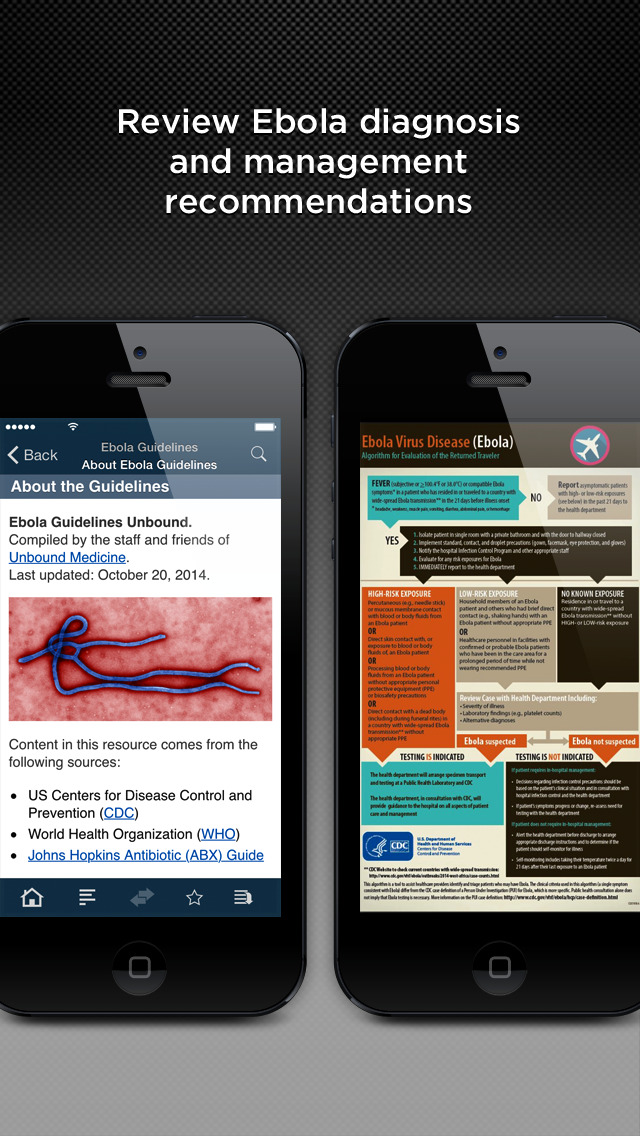

Relief Central is a free mobile and web resource developed by staff and friends of Unbound Medicine. It includes the latest versions of The World Factbook from the CIA, CDC Health Information for International Travel (The Yellow Book), the Field Operations Guide from USAID, Prime PubMed Search, and Relief News from the Red Cross, United Nations, US Centers for Disease Control, CDC, FEMA, and more.

CDC YELLOW BOOK (Health Information for International Travel)

The Yellow Book presents advice on any travel health issue including vaccinations, essential trip planning and safety tips, prevention of an expanded list of travel-related infectious diseases, altitude illness, motion sickness, sunburn, medical tourism, and much more.